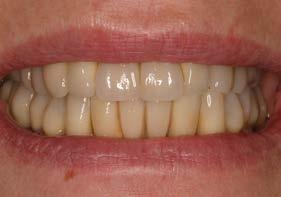

La paciente continúa bajo seguimiento periodontal. A los 5 años se observa estabilidad clínica del tratamiento (Figuras 22–24), sin recesiones gingivales ni pérdida ósea asociada en las imágenes clínicas y radiográficas.

Un año más tarde, al finalizar el periodo de seguimiento (24 años), las fotografías intraorales evidenciaron ligeras alteraciones de los tejidos blandos, con pequeñas troneras abiertas,

más evidentes en los dientes naturales conservados que en las restauraciones implantosoportadas. A pesar de estos cambios, el resultado global se consideró satisfactorio desde el punto de vista funcional y estético, especialmente en comparación con la situación clínica y radiográfica inicial previa al tratamiento (Figuras 26–31).

Los hallazgos observados en el caso presentado se alinean con esta evidencia, al documentar la estabilidad durante 25 años tanto de los implantes como de dientes que, en el momento inicial, presentaban un pronóstico claramente comprometido. Esta evolución refuerza la idea de que la pérdida ósea inicial no debe considerarse un criterio absoluto de exodoncia, especialmente cuando existen posibilidades reales de control de la enfermedad y seguimiento continuad.36-39 Asimismo, el hecho de que las alteraciones tisulares finales se manifestaran de forma más evidente en los dientes naturales conservados que en los implantes subraya la naturaleza dinámica del periodonto a largo plazo y la necesidad de reevaluaciones periódicas del pronóstico, incluso bajo condiciones óptimas de mantenimiento.22,23,36

Figuras 30 y 31. Comparativa inicial y final a los 25 años de seguimiento, que muestra la estabilidad alcanzada tanto en los dientes conservados como en los implantes.